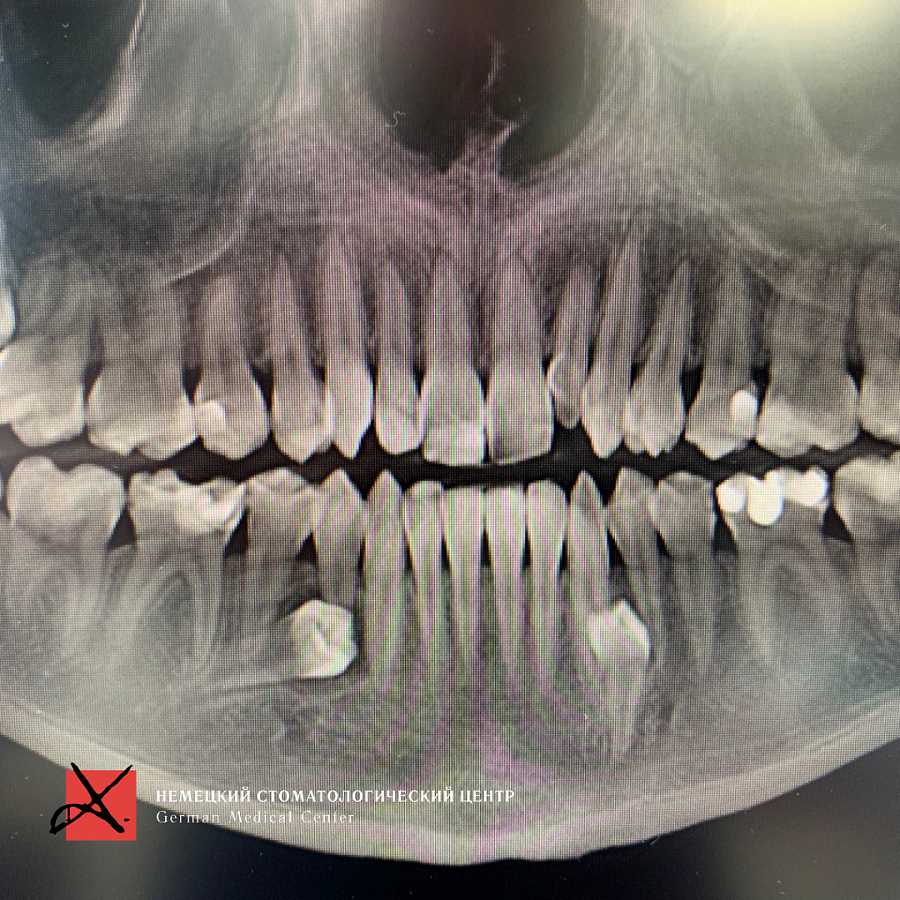

картинка

Этапы лечения

Зубы были удалены через окошко в кости, сделанное изнутри полости рта со стороны языка. Заживление прошло отлично, пациент ни на что не жалуется, соседние зубы не были повреждены.

На данный момент пациент продолжает ортодонтическое лечение.